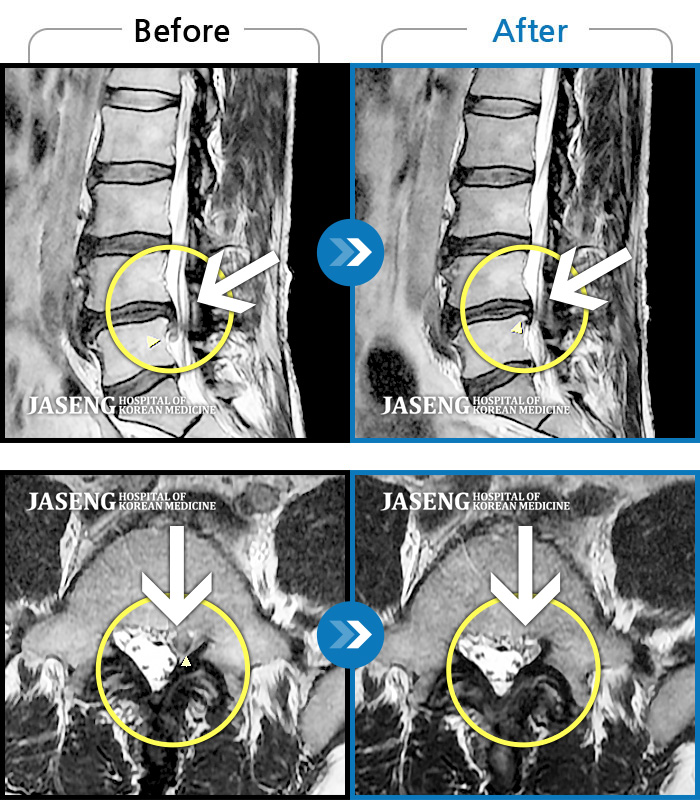

원재균원장님을 칭찬합니다 추간판탈출증으로 입원해서 치료 받는동안 항상 밝은모습 으로 허리와다리 통증있는 부분을 친절하게 설명해주시고 걱정해주셔서 너무 감사합니다 원장님의 극진한 치료 덕분에 좋은결과로 퇴원하게 되었습니다 감사합니다^~^

저는 허리디스크 파열로 자생한방병원에 입원하게 되었습니다 저를 치료해주시는 원장님은 원재균원장님이시구요 원장님은 항상 환자와 소통하기를 원하셔서 환자의 아픈부분 부분을 세세히 물어보시고 정성으로 치료해주시는 분입니다 침을 놓으실때도 꼼꼼히 정확하게 놓으시고 환자의 상태를 살펴주심니다 진료하실때 원재균원장님께서는 환자에게 도움을 주시려는 진심이 느껴졌습니다 진료를 마치고 회진을 도실때도 겉치레가 아진 진심으로 환자를 대하시고 스트레칭 방법이나 병원에서의 운동방법등을 세세히 설명해주셨습니다 저에게는 많은 도움이 되었구요 원재균 원장님 감사했고 고마웠습니다 항상 건강하십시요

저는 디스크 파열로 자생한방병원에 입원하게 되었습니다 감사하게도 원재균원장님의 진료를 받게되었구요 원장선생님은 다정다감하시고 환자의 말에 귀를 기울이셔서 어떻게 치료할까를 많이 생각하시고 침술을 배푸실때도 정성을 다하고 꼼꼼히 하시는 모습에 너무 감사했습니다 저녁 회진때도 형식적이 아닌 진심으로 한마디라도 환자에 보탬이 되게 말씀해주시는것 같았습니다 그말씀 듣고 스트레칭도 하고 치료를 받으니 정말 놀랍게도 상태가 많이 호전되어 퇴원하게 되었습니다 선생님 치료받는 동안 너무 감사했고 고마웠습니다 항상 건강하십시요^^